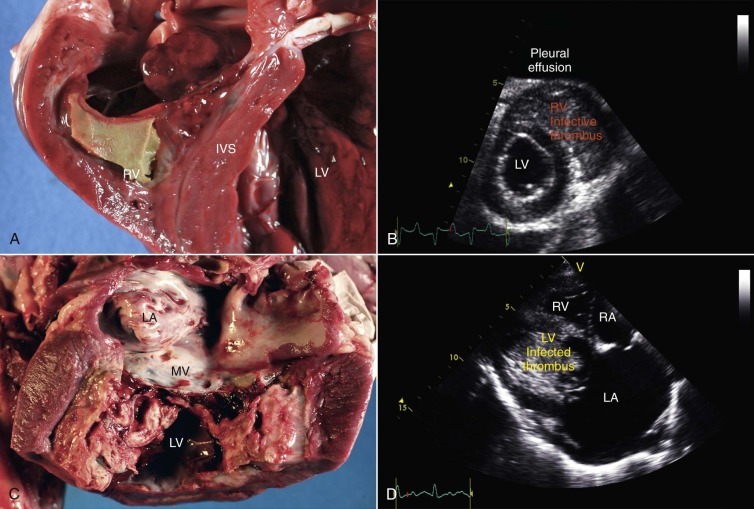

Endocarditis is an important but, fortunately, infrequent disorder of camelids.26, 27, 28 In most domestic animal species, endocarditis lesions are mainly confined to the cardiac valves and mural lesions are uncommon. In camelids, mural lesions within the ventricles have been observed more often and are more dramatic than valvular lesions, at least in the population of animals evaluated at Oregon State University (Figure 36-17 ). In our experience, the endocardial surface of the right ventricle is more commonly affected than the left, although both ventricles are affected in half the cases. Often, the leaflets of the AV valves become embedded within the thrombotic material, with the tricuspid valve slightly more commonly affected than the mitral valve. It is usually difficult to identify a remote source of infection as the primary cause of endocarditis, although preexisting abnormalities have been identified in several reports. Bacterial organisms may sometimes be recovered either via blood culture or at necropsy, but it is often not possible to recover microorganisms before or after death.

Figure 36-17.

Mural endocarditis in alpacas is manifest as the deposition of infected fibrin thrombi on the walls of the right (A and B) or left ventricles (C and D), often with concurrent involvement of the ipsilateral atrioventricular valve. Note the near-obliteration of the right and left ventricular lumens noted both at necropsy (A and C) and by echocardiography (B and D).

Physical occlusion of the ventricular lumen, which causes restricted ventricular filling, and incompetence of the AV valves contribute to the development of clinical signs.

Recumbency, depression, lethargy, exercise intolerance, colic, and abdominal distention are common presentations in affected animals. Murmurs are audible if the AV valves are affected and jugular distention may be present. Distention of the abdomen may be caused by ascites and hepatomegaly, and in some cases, the enlarged liver may be palpated through the right flank. Hepatomegaly may also be detected ultrasonographically. In some cases, the liver completely fills the right paralumbar fossa. Blood work changes are variable. During quiescent periods, the complete blood cell count (CBC) and the biochemistry panel may be normal. Neutrophilia, hyperfibrinogenemia, and hyperglobulinemia may also be seen. The primary source of infection may be more instrumental in determining blood abnormalities than endocarditis. We have seen increases in liver and muscle enzymes, azotemia, and degenerative leukograms in connection with diffuse hepatic infection, hepatomegaly, and right heart failure. Abdominocentesis or other pertinent tests may also reveal information about the underlying inflammatory disorder or may just reveal copious ascites.

Definitive diagnosis is best achieved by echocardiography (see Figure 36-17). Treatment has not been rewarding, in part because of the advanced nature of the disease on detection. Antibiotics, antiinflammatory drugs, and fluids are the most common treatments.